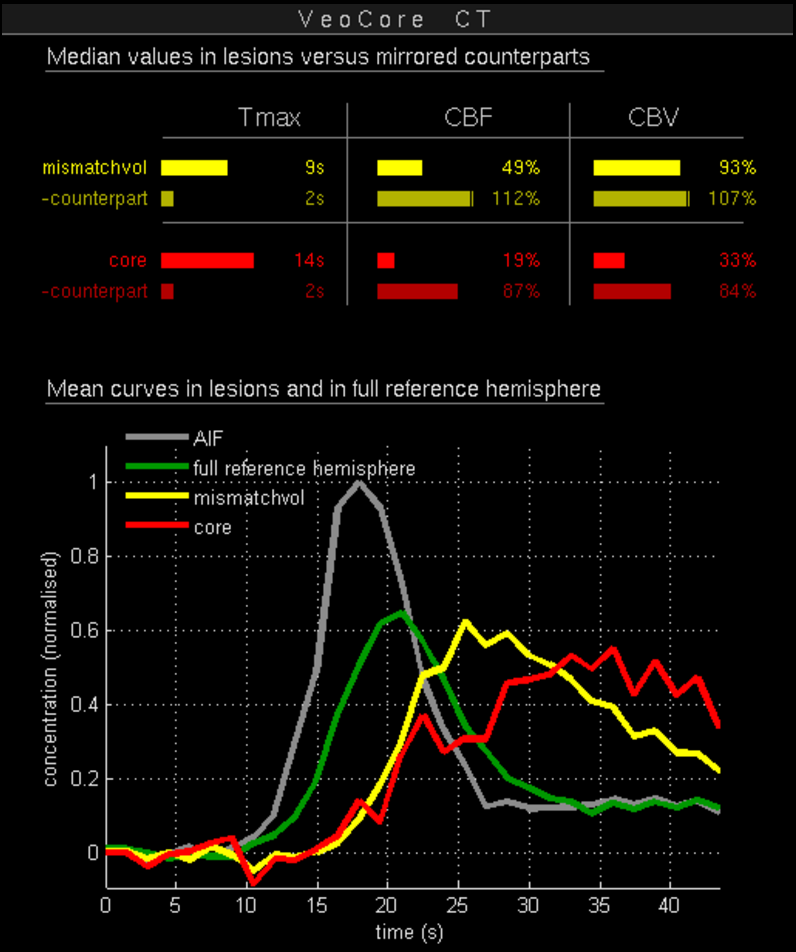

Des Weiteren ist mRay in der Lage eine Verarbeitung von Bildern durchzuführen und so Veränderungen bzw. Anomalien in Geweben zu finden, zu visualisieren und zu quantifizieren. Das Bildverarbeitungsmodul mRay VEOcore kann verwendet werden, um Bilder des Gehirns von Bildgebungsmodalitäten wie CT, Perfusions-CT oder MRT mit diffusionsgewichteter Auswertung (DWI) zu prozessieren. Als Ergebnis werden Kontrastveränderungen über die Zeit als farbige Perfusionskarten angezeigt, dies beinhaltet auch flussbasierte Parameter und Gewebeblutvolumen Berechnungen.

Die Perfusionsanalyse von Aufnahmen des Gehirns ermöglicht die Darstellung und Quantifizierung von minderdurchblutetem Gewebe (Penumbra), nicht-durchblutetem Gewebe (Kerngewebe) und dem Mismatch-Ratio zwischen den beiden Werten. Die berechneten Werte können der Unterstützung bei einer Entscheidungsfindung dienen, die auf der Beurteilung des Ausmaßes der Schädigung von Geweben basiert.